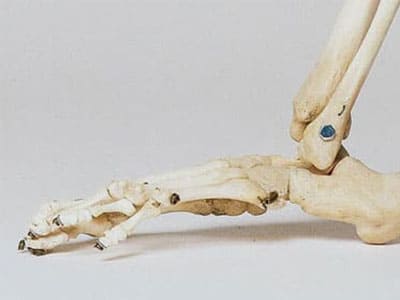

관절염과 관절통 개선

시서스의 항염증 작용은 관절염이나 관절통 등의 증상을 완화시키는데 도움을 줍니다. 관절통이 있는 남성을 대상으로 진행된 연구 결과에 따르면 시서스를 복용했을 경우 부기나 관절통이 감소되었습니다. 이와 유사한 연구는 몇 번 더 진행되어 시서스 추출물이 골관절염이나 류머티즘 관절염을 발생시키는 염증 인자를 감소시킨다고 알려져 있습니다.